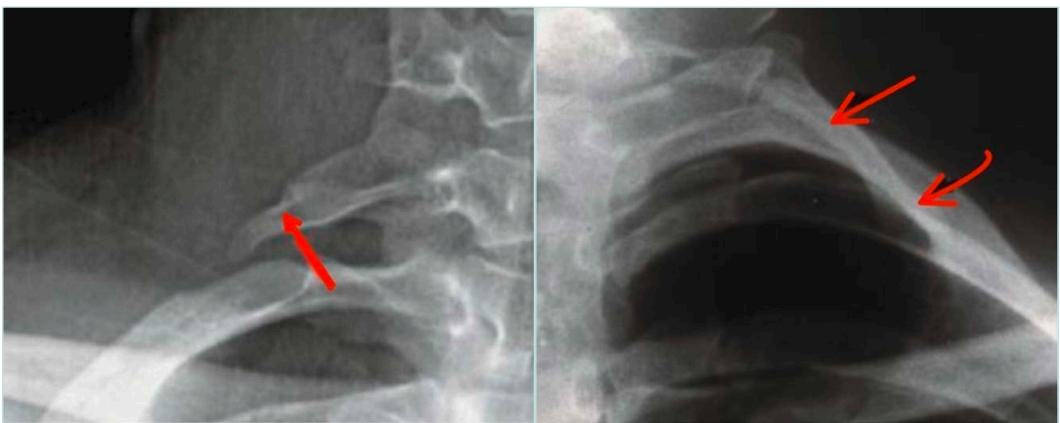

Plain radiography

Plain radiography is used adjunctively to detect cervical ribs, elongated C7 transverse processes, or posttraumatic bone healing that may alter thoracic outlet anatomy. It is not definitive but is often a useful first step (Figure 7).

Figure 7. X-ray with elongated transverse process (right image) and complete cervical rib (left image).